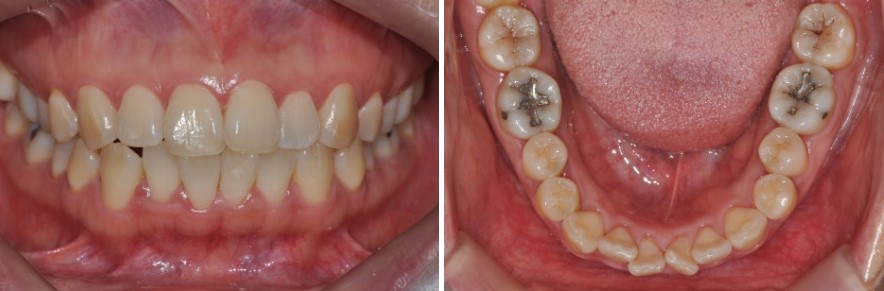

예를 들어,

돌출과 치아 배열 때문에 내원하신 30대 여성 환자분의 경우,

이때 치간삭제를 시행하고 공간을 다시 닫아 주면서

블랙 트라이앵글이 완전히 사라지지는 않더라도

눈에 띄게 크기가 줄고, 치아 사이가 더 긴밀하게 붙어 보이는 효과를 얻을 수 있습니다.